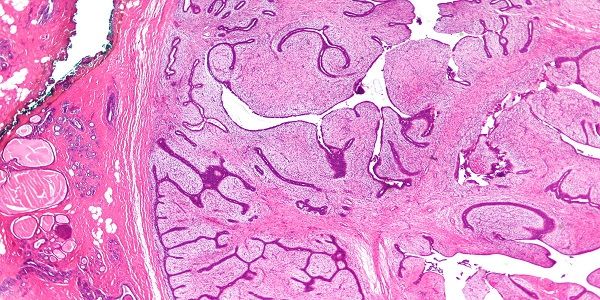

Filloides Tümörler

Filloides tümörler memenin nadir görülen fibroepitelyal lezyonlardır. Her yaşta görülebilirler fakat sıklıkla 35-55 yaş aralığında sık...